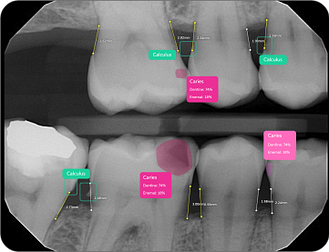

Caries Detection

The best for last and arguably the most well-thought-out feature. Especially with the tooth segmentation mode, which makes it easier for patients to understand their diagnosis and treatment plans.

The system uses two shades of pink to indicate potential caries:

- Light pink: Incipient caries (100% in enamel) - we will often review

- Darker magenta: Caries extending into dentin - we need to restore

The system even provides a percentage breakdown of enamel vs. dentin involvement. I have been blown away by its accuracy while using it, and it makes something that feels quite subjective (reading shades of grey) into a science.

This feature is very useful for patient education and deciding between preventive measures and restorative treatment. However, remember that radiographic evidence alone is not always sufficient for a definitive caries diagnosis.

Calculus Detection

Green squares highlight areas of radiographic calculus. This tool is useful for hygienists and dentists in treatment planning and patient education.

Quite self-explanatory and the system didn't seem to miss often, if ever.